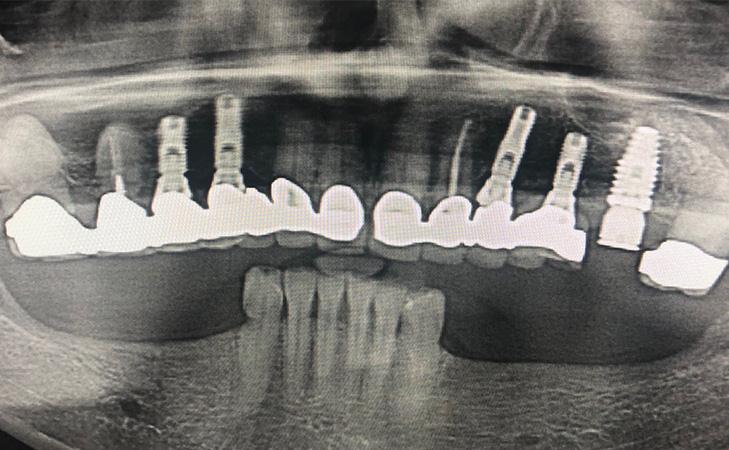

This 74 year old patient was unhappy with her current smile and the existing teeth were unsalvageable. Utilizing computer planning and guided implant placement, the teeth were extracted and implants were placed on the same day. 6 months later, final bridges were made and the patient was thrilled with her new smile.

This patient presents missing right and left lower jaw teeth. Jaw bone was regenerated using the latest techniques and 3 dental implants were placed on each side for permanent crowns.